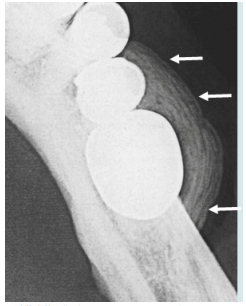

9.如下圖所示,該唾液腺體呈現ball in hand之顯像,則最有可能之診斷為何?

(A)sialolithiasis (B)sialoadenitis (C)sialodochitis (D)tumor of salivary gland